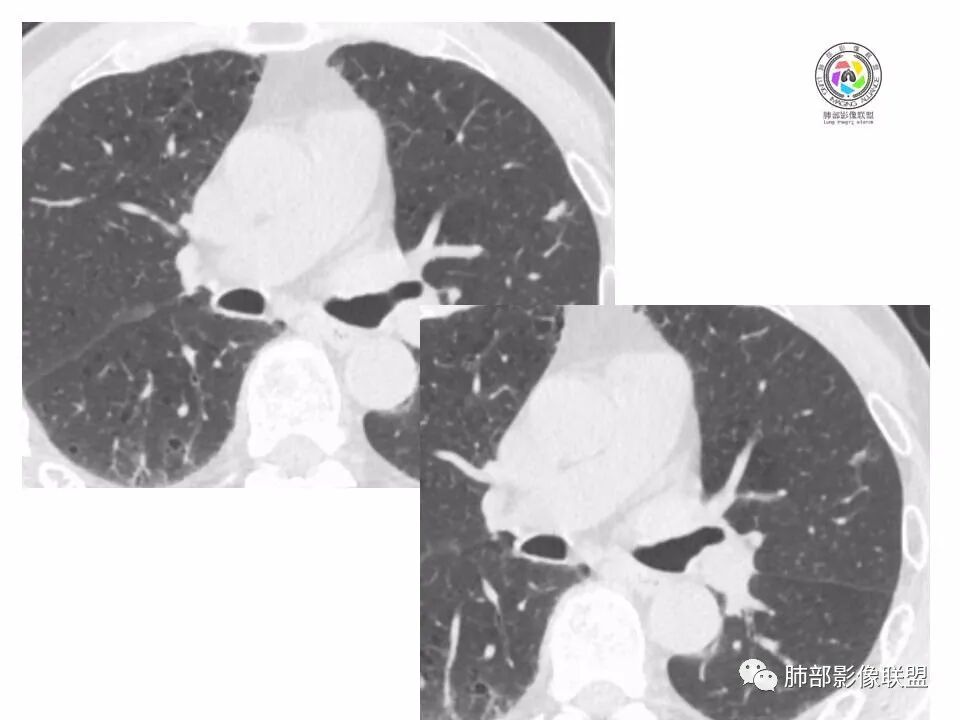

左肺上叶小结节,边缘毛糙,血管集束,支气管截断,强化较明显,但U型凹陷,部分边缘平直,总体感觉恶性大于良性,首选腺癌,鉴别炎性肉芽肿。

左上肺结节,月牙征,边缘纠集有收缩力,小空泡,血管增粗进入,纵隔淋巴结增大,考虑恶性,隐球菌待排。

老年男性,左上肺结节,边缘毛糙,临近血管进入增粗,内部隐约可见小空泡或远端扩张支气管,血管集束并伴月牙铲,有个横断界面看似像脐凹征,常规考虑腺癌,鉴别隐球。

结节,分叶,边缘毛糙,小空泡,血管集束并伴月牙铲,有强化,老年男性,考虑腺癌,建议复查除外结核。

左肺上叶混合密度结节,边缘见边缘清楚磨玻璃,分叶,U型凹陷,首先考虑腺癌。

左肺上叶结节影,边缘可见分叶,血管集束及月牙铲征,病灶内见小空泡影,考虑腺癌可能。

结节密度不均匀,混合磨玻璃结节,大部分实性部分,边缘清,月牙铲征,肿瘤微血管征,考虑肺癌。

老年男性,体检发现左肺上叶结节,周围浅分叶伴磨玻璃影,有血管相连,U型凹陷,纵隔见肿大淋巴结,考虑为恶性,腺癌可能。

左肺形态不规则结节,边缘收缩,毛刺,有月牙铲,纵隔窗比肺窗小,不密实,近段血管与病灶相连,强化不明显,老年男性,综合考虑,恶性,腺癌,鉴别炎性结节。建议穿刺。

老年男性,左肺上叶结节,边界清,不规则,有毛刺,血管集束,空泡,边缘有气肿带,考虑腺癌,鉴别肉芽肿。

左肺上叶小结节,边缘毛糙,血管集束,支气管截断,有月牙铲,首选腺癌,鉴别炎性肉芽肿。

左上肺实性小结节,短毛刺,月牙铲,似见小空泡,血管集束,有轻度强化,首先考虑腺癌。

老年男性,肺气肿背景,左肺上叶小结节,大部分边缘平直,部分边缘膨隆,局部可见月牙铲,边缘少许磨玻璃,边界清晰,血管进入,轻度强化,首先考虑腺癌,常规抗炎后复查,除外炎性结节。

左上肺结节,短毛刺,空泡,月牙铲,脐凹征,考虑腺癌。

左肺上叶混合密度结节,边界清,分叶,毛刺,血管进入,月牙铲,有强化,首先考虑腺癌,有平直边,收缩力不明显,常规先抗炎。

左上肺结节分叶,边缘毛糙,小空泡可能,血管集束,月牙,纵隔窗面积小于肺窗,有磨玻璃成份,有强化,老年男性,白细胞高,恶性的征象都有,但磨玻璃的形态和边界不好评估,实性为主,看形态和边缘局部较散缺乏饱满感,顶着压力反着来猜炎性可能大。复查不消失会考虑腺癌或黏液腺癌。

老年男性,肺气肿背景,左肺上叶实性结节,边界清,边缘平直为主,细长毛刺,较明显强化,考虑炎性病灶,隐球?

老年男性,左肺上叶结节,边缘可见长毛刺、较软,并可见分叶,周围可见清楚磨玻璃密度,内可见空泡征,增强后呈均匀强化,良恶性征象都有,感觉收缩力不强,化验白细胞偏高,建议抗炎治疗后复查除外腺癌。

老年男性,左肺上叶混合密度结节,空泡,分叶,血管集束,有强化,考虑腺癌;细长软毛刺,血管走行自然,边缘有平直收缩,白细胞高,肿标正常,考虑炎性结节。猜炎性结节,鉴别腺癌。

左肺上叶前段mGGN,边缘见毛刺及月牙铲,考虑腺癌,需要薄层图像确认所见征象。

左肺上叶结节,分叶,边缘毛糙,小空泡,月牙铲,有强化,考虑浸润性腺癌,鉴别炎性肉芽肿。

患者老年男性,体检发现。查癌胚抗原不高。血常规血象升高。胸部CT:肺气肿背景,左肺上叶近胸膜下实性结节,边缘光滑,边界清楚,可见毛刺、血管集束、月牙铲征象,增强不明显,内可见低密度区,综合考虑恶性病变,腺癌可能大,鉴别结核及炎性结节。

老年男性,左肺上叶结节,周围浅分叶伴磨玻璃影,有血管相连,月牙铲。纵隔见肿大淋巴结,但白细胞高。腺癌首先,需排除炎性假瘤。抗炎治疗后复查。

老年男性,体检发现左肺结节,分叶、脐凹、月牙铲及月牙铲附近有边缘清楚的磨玻璃影,上述征像均指向恶性肿瘤,有疑问的地方:毛刺软无力,无胸膜牵拉及白细胞计数升高。整体是腺癌,需要抗议后复查以排除炎性病变。

图片有限,左肺上叶结节病灶,有张力,有收缩及小泡征,边缘可见月牙征,周围长毛刺及血管集束征,增强目测有中度以上强化,首先考虑恶性病变,腺癌。

左肺上叶前段小结节,边缘稍毛糙,月牙铲,血管进入可疑脐凹征,小空泡?增强有强化,老年男性,要高度警惕腺癌,但感觉毛刺偏细软,周围磨玻璃不明显,常规查隐球菌荚膜抗原除外隐球菌,血象高,抗炎后短期复查除外炎性结节。

左肺上叶mGGN,边缘收缩平直为主,肺窗显示清楚,纵隔窗体积缩小,未见胸膜牵拉,倾向感染性结节,隔期复查。